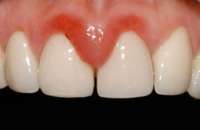

14736108869120.jpg (303Кб, 1824x1368)

Во сколько примерно обойдется лечение такой хуйни на передних зубах и за сколько походов?

Аноним 11/09/16 Вск 20:04:49  515332

>>515322

1-2 захода, 10-15к